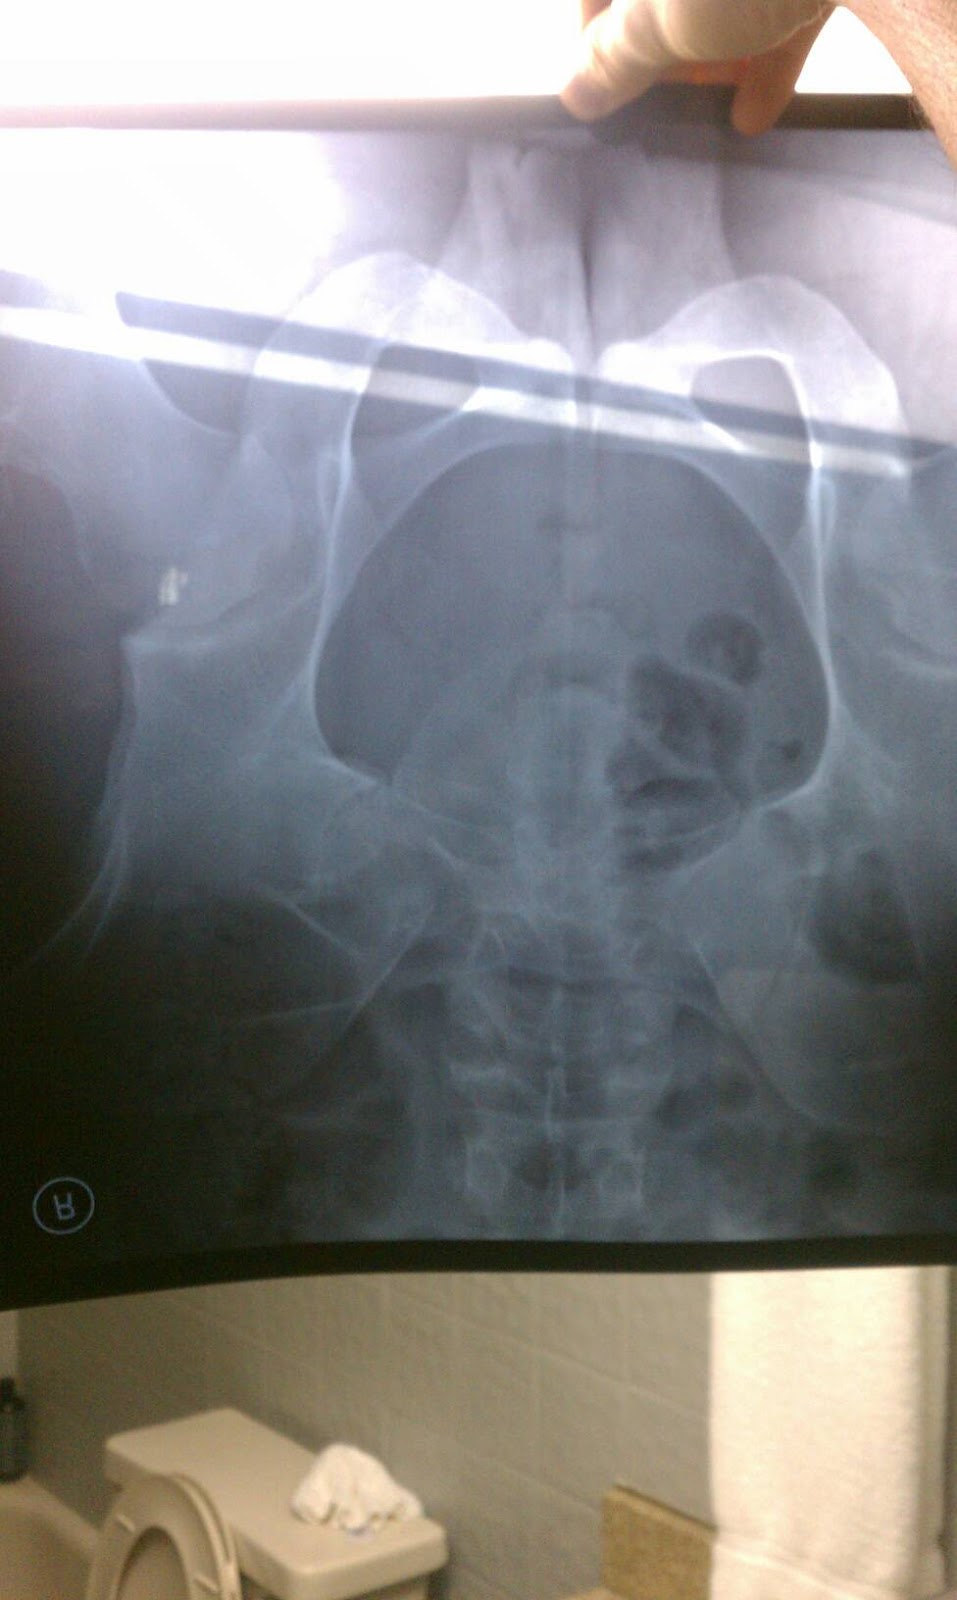

Niagra "FALL"

for those who haven't heard yet, I took quite the digger onto my left hip yesterday afternoon. I was literally 5 miles away from the u.s. boarder when I hit these extremely slick trolley tracks on a main road in thoroid, Ontario. I was going so fast I didn't see it coming. I even crossed over the trolley tracks at the appropriate angle so that my wheels wouldn't get caught between the road and the rails (picture the T tracks along the street in Boston and that's basically what I was dealing with). It had been raining off and on all day so the tracks must have been unusally slick. Nonetheless, I fell. I fell exactly the same way I fell on day 3, almost to a tee. As I'm lying in the middle of the road, I realize I can't even move my left leg. I know my guitar must he in pieces. All I can think of is "how in the hell am I going to get back to Boston?" A few cars pull over to assist me and one happens to be an off duty firefighter from the town over. They're dragging my bike off of me and giving me a lift up onto ny feet. My glasses broke into 3 pieces, my water bottles were all over the place, and as I stood I had a real hard time putting any weight on my left leg. The emt's showed up, and for the first time in my life I was loaded onto a stretcher and into the back of a ambulance. The two emt's, carolyn and brianne, were fascinated by my trip and took excellent care of me. Because I was so close to the boarder, they took me to niagra falls hospital in Canada to get checked out. After a long assessment of the situation, it was decided amongst many individuals that I was going to stay in that hospital for the night...until I heard how much it was gonna cost haha. Clearly I was not dying but I was in a good amount of pain and could definitely not walk anywhere with all of my gear and my bike. Carolyn and brianne arranged a cab for me and helped me load everything in for me as I have basically been in a wheelchair for about an hour at this point purely because they didn't have crutches at the hospital. I feel like every hospital should probably have a room like, oh I donno, 200 square feet that is stacked to the ceiling with crutches. I think that would be in their best interest in my opinion haha. Anyways, they must've told the cab driver my whole story because the guy wanted my autograph. He told me what I'm doing is newsworthy and that he wanted to go down to the niagra gazette or something to have them write an acticle on me. This guy was too funny. Told me the whole history of niagra falls, told me about how he likes to mess around with patriots fans when they come up here to see them play the bills. He was also one of probably 5 people this whole trip that were like "you're from Boston? Where's you're accent? You don't have one". So we get across the boarder, which was wayyy easier than getting into Canada, which was nice considering my leg is like throbbing. Get the an American hospital and as I fanagle myself out of the cab the first thing I become aware of is how much of a JERK this nurse is being to me. Snapping at me like I'm making her do her JOB or something. To be honest with you I wanted to hop out of that wheelchair and crawl out of the hospital because she threw such bad vibes off at me. Turns out, she ended up being really nice once she stopped being a giant crabbypants. She let me take my xrays home with me and even got me some ginger ale. She also gave me two shots. One of which was in my tush. That was a first for me haha. I get xrays, I get a cat scan (also a first for me. Gotta love that radiation), and then I waiting 4 hours for my results. My buddy Ian was nice enough to come pick me up even thought he had to work at 6am and I felt so bad because he arrived at 11:30 when I thought I was going to be done. We didn't leave until 3:30am. I didn't break or fracture anything in my leg. I have a hip contusion. Unlike Canadian hospitals, we have crutches, so they gave me a pair. First time ever on crutches, too. This was just a day full of firsts for me! Im currently working on my music in the hotel Ian is staying at I'm Batavia, NY, waiting for my heroes Jesse mosher and Amy Allen to come scoop up my body full of hurt and bring me back to my home. Back to Boston. Wounded in more ways than one, but spirit high. I could not have asked for a more eventful and life-changing event to experience. This trip has been wild with its ups and downs, but all in all, I biked through pouring rain, through mountains, through wind, along rolling countrysides. I've seen interesting animals, met interesting people, had interesting thoughts, and pushed the limits of who I thought I was to the very breaking point. Here i am, on the other side. Emerged not quite how I pictured, but I have emerged nonetheless. A more defined individual. A more focused mindset. A sharpened persepective. I have so much material to write about. So much to express for this album, this gift to all of you who donated and who have followed me on this incredible journey. I will continue to do updates here and there, and I also did not forget about certain peoples postcards! If you donated $25 or more, please email me your mailing info so I can still send you your postcard. I have some videos for those who donated more than that, but I have not been able to figure out how to change the file type on my phone, so I will send those once I'm home. Thank you all again for the wonderful support!